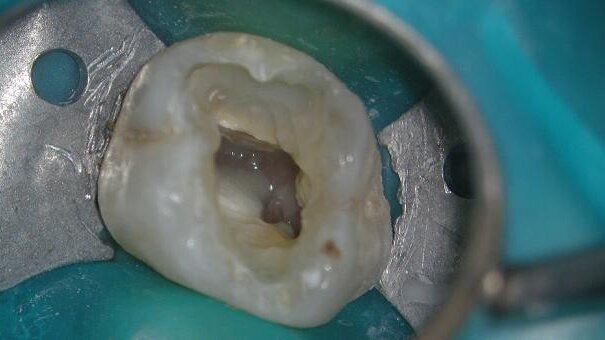

The patient came to our clinic with acute apical periodontitis around tooth 26. When examined clinically and radiographically, the tooth showed a large composite filling next to the distal pulp horn (Figs. 3 & 4). The periodontal examination did not find any irregularities; however, the tooth was extremely painful in vitality tests. Initially, I intended to replace the composite filling. After removing the old composite filling, I noticed secondary decay that reached up to the pulp chamber (Fig. 5) and I subsequently decided to pursue endodontic treatment. The treatment was performed in one session. Four canals were identified (MB, MB2, DB and P; Fig. 6). The main problem was in the MB2 canal, which had a 90-degree curvature. The treatment was performed with TF 25.06 in the MB2 canal and with TF 25.08 in the other canals (Fig. 7). As a final irrigant, I used SmearClear (SybronEndo). After obturating the canals with warm vertical condensation using the Elements Obturation Unit (SybronEndo; Fig. 8), the canals were sealed with a coloured composite (RxFlow, Dental Life Sciences; Fig. 9). Finally, the tooth was restored with a composite filling (Fig. 10) and the control X-ray was taken (Fig. 11).